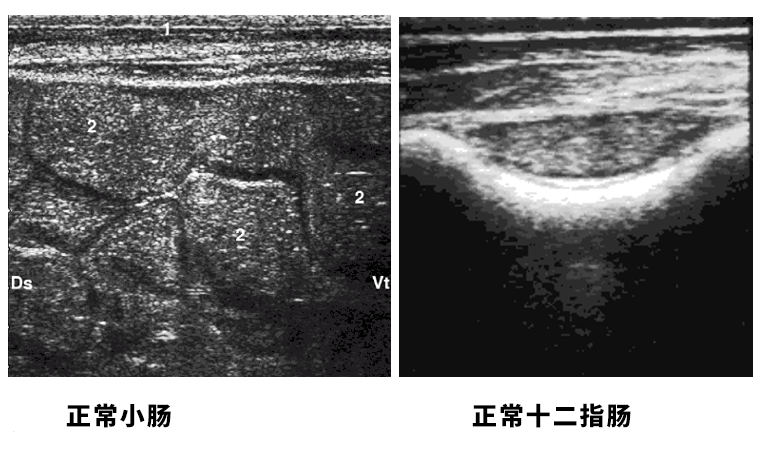

牛用B超机检测牛的小肠:

十二指肠包裹在右腰旁窝中央的网膜中。

牛用B超检测牛的小肠